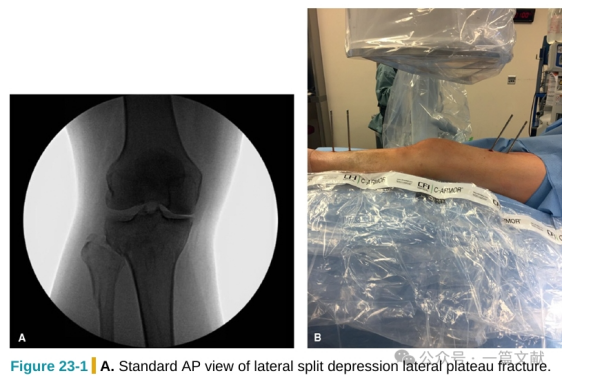

Intraoperative Fluoroscopic Techniques for Tibial Plateau Fractures

Intraoperative Fluoroscopic Techniques for Tibial Plateau Fractures